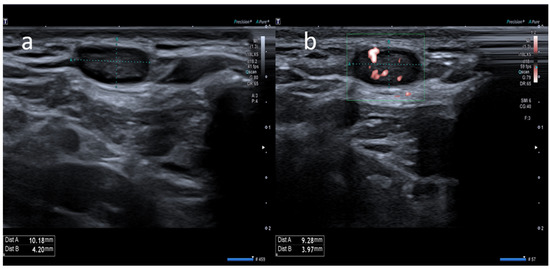

Atypical Sites of Lymphadenopathy after Anti-COVID-19 Vaccine: Ultrasound Features

- Cocco, G.; Pizzi, A.D.; Fabiani, S.; Cocco, N.; Boccatonda, A.; Frisone, A.; Scarano, A.; Schiavone, C. Lymphadenopathy after the Anti-COVID-19 Vaccine: Multiparametric Ultrasound Findings. Biology 2021, 10, 652. [Google Scholar] [CrossRef] [PubMed]